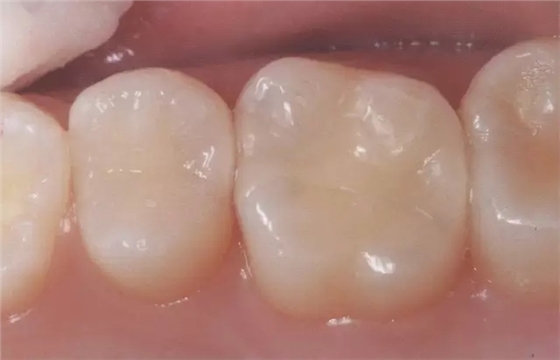

圖2右5進(jìn)行了全瓷嵌體修復(fù),為了使受力均勻,線角需要呈圓弧狀。

圖3 全瓷嵌體的修復(fù)(右56)。鄰接面產(chǎn)生齲齒的情況(上段,中段左),去除齲齒,并佩戴嵌體(下端)。